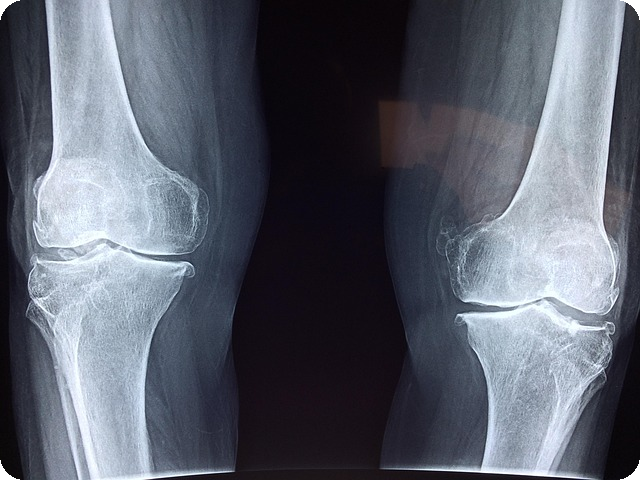

글루코사민은 관절 건강을 유지하는 데 매우 중요한 영양소입니다. 나이가 들수록 우리 몸에서 연골이 점차 줄어들면서, 이 성분의 필요성이 더욱 커지게 됩니다. 이번 섹션에서는 글루코사민이 갖는 다양한 역할과 그 필요성에 대해 알아보겠습니다.

글루코사민은 연골을 형성하는 핵심 성분입니다. 관절 부위에서 연골이 마모되지 않도록 돕는 역할을 하며, 이렇게 연골이 보호되면 관절이 부드럽게 움직일 수 있습니다. 관절이 사용되는 과정에서 발생할 수 있는 마찰로부터 연골을 보호하여, 관절 통증의 발생을 예방하는 데 중요한 도움을 줍니다.

관절 통증은 나이가 들거나 혹은 운동으로 인해 심해질 수 있습니다. 글루코사민은 염증을 줄이고 통증을 완화하는 효과로 알려져 있습니다. 과거 연구에서는 글루코사민이 관절염 진행 속도를 늦추는 데도 효과적이라는 결과가 있었습니다. 규칙적으로 글루코사민을 섭취하면, 관절 통증 콤플렉스에서 해방될 수 있는 기대를 할 수 있습니다.